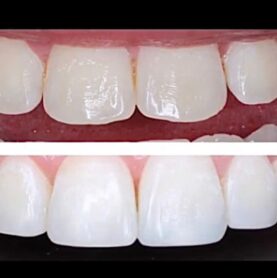

Galería de Tratamientos

Cada sonrisa cuenta una historia única. Descubre las increíbles transformaciones que hemos logrado con nuestros pacientes a través de documentación fotográfica profesional que captura cada detalle.